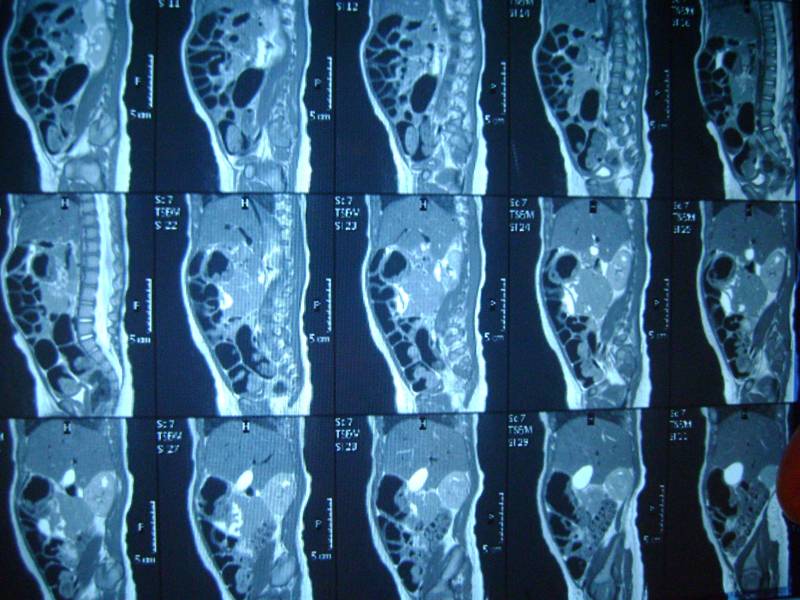

еще